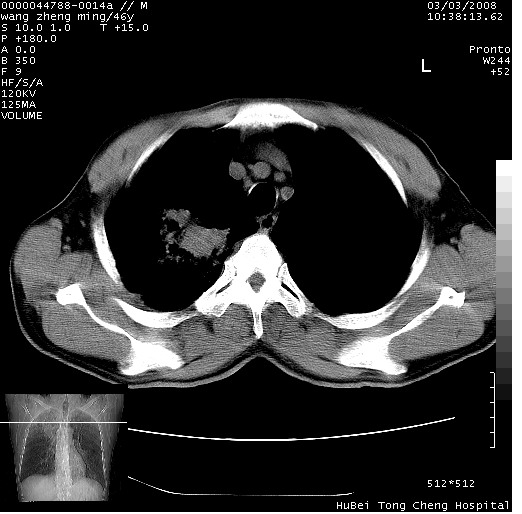

以下是引用卜一在2008-3-22 1:37:00的发言:[br]右肺实质性肿块,边缘不整,明显见毛刺征 分叶征及胸膜凹陷征,右上叶支气管明显变窄,远端散在的片状 斑片状实变影。另:左肺门较大肿块,支气管受累 变窄,远侧见阻塞性肺炎。纵隔内见肿大淋巴结。多考虑:右肺周围性肺癌伴左肺门 纵隔淋巴结转移!